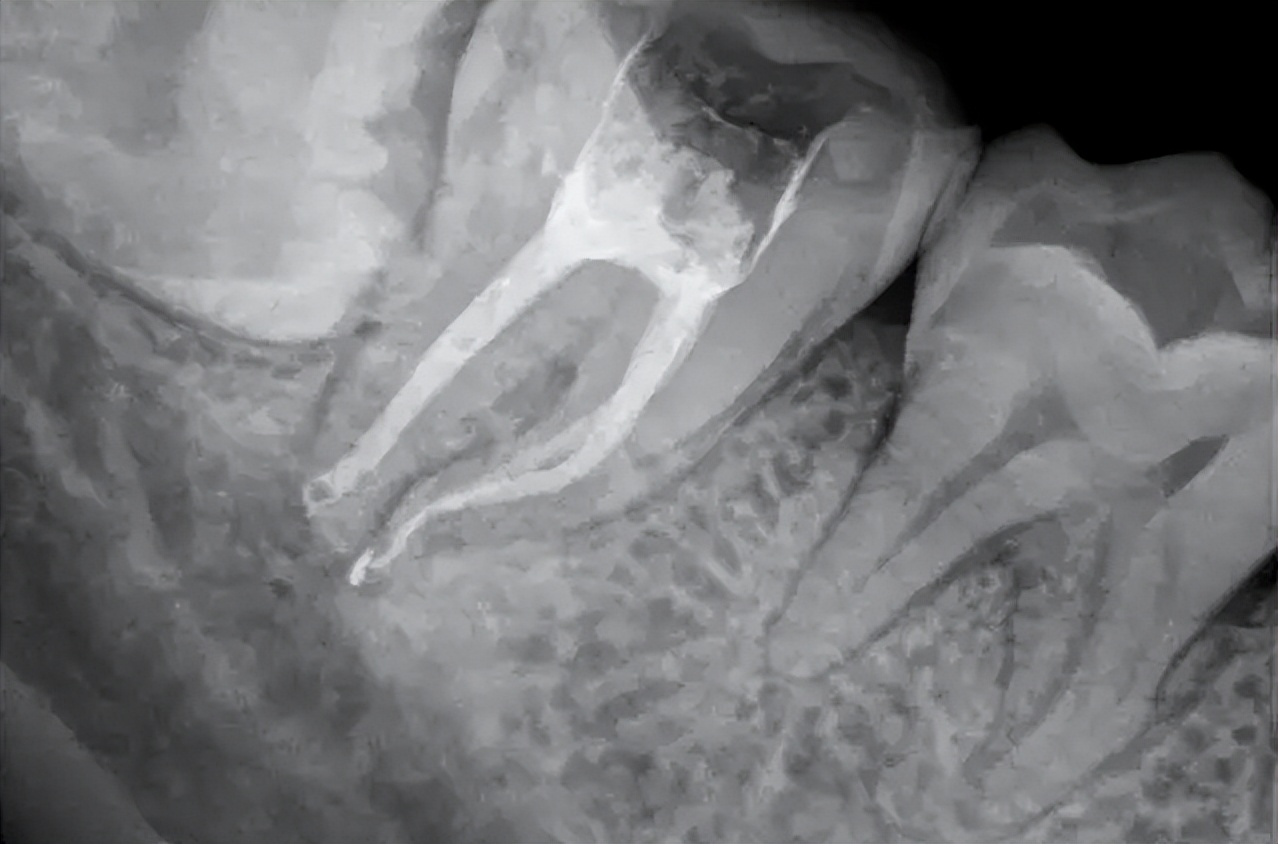

2、通过拍片检查

部分牙髓坏死的人在拍摄X光片时是能够较明显看出牙齿并伴有龋坏的情况。